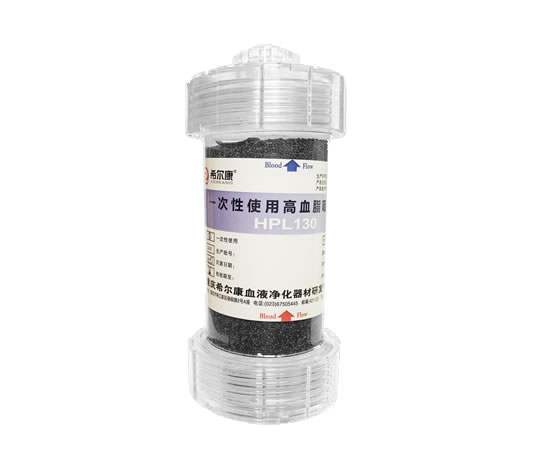

一次性使用高血脂吸附柱

在研产品

一次性使用高血脂吸附柱

主要用于各种原因所致的“高脂血症”。